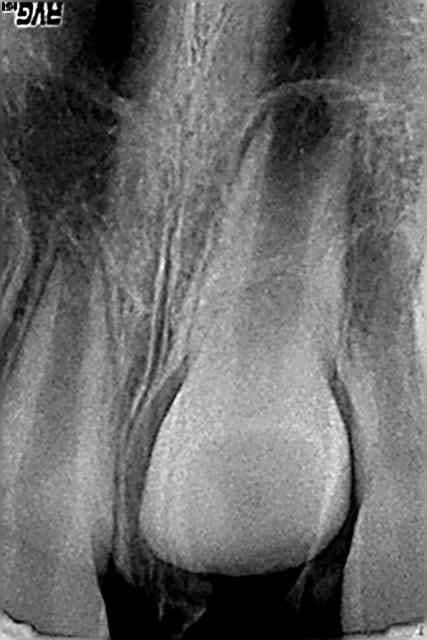

Je réactive ce message avec mon patient vu à 4 mois de la consultation précédente du mois d'aout:

J'avais fait deux séances d'hydroxyde de calcium en août et j'ai obturé sans pression avec un IRM. Il y avait une communication endo-parodontale juste sous le collet en vestibulo distal au départ) visualisée en soufflant légèrement avec la seringue à air.

Il va avoir 5 ans dans quelques jours.

Voici le résultat en image à 4 mois exactement. Aucune douleur, pas de mobilité dentaire.

Vu que je ne suis pas très objectif sur ce cas clinique (c'est mon fils) et que pour l'instant tout va bien pour lui et que je n'ai pu me résoudre à extraire rapidement la dent (pour l'instant...) comme le conseillait ploc...

Merci de me donner votre avis avec peut être plus d'objectivité... Dois je réintervenir rapidement sur la dent? L'obturation semble étanche.